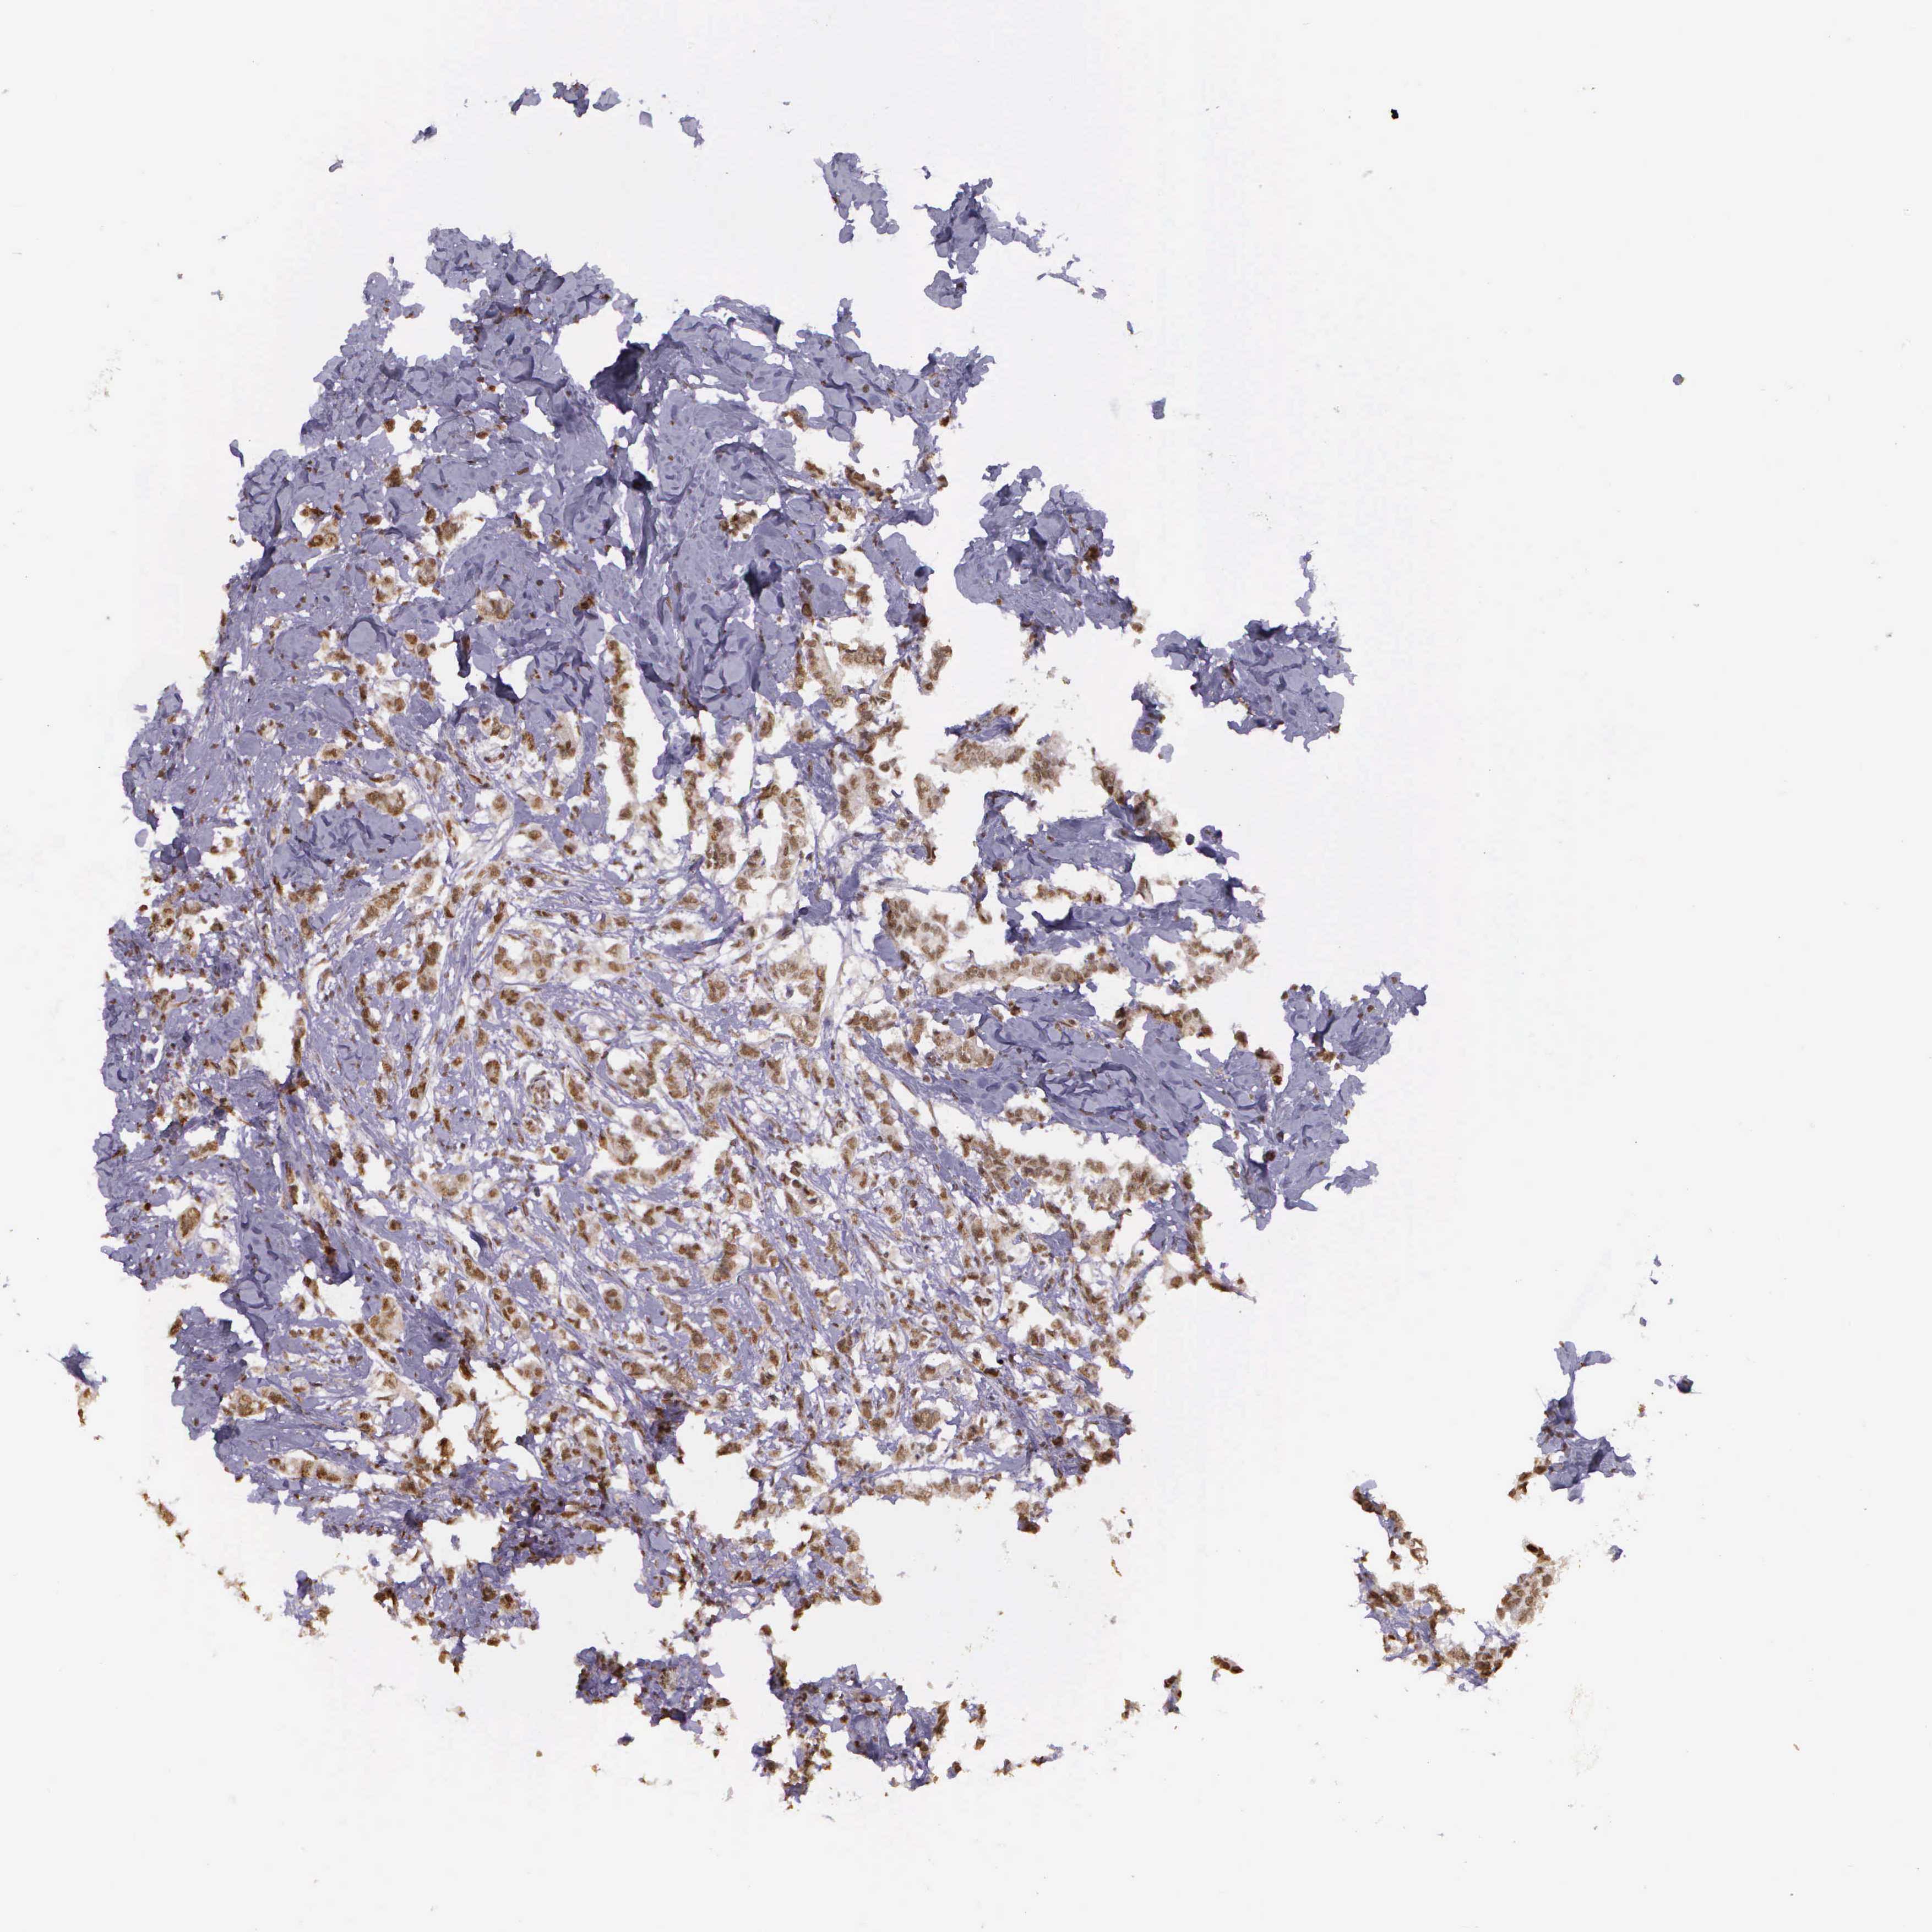

CANCER BREAST CANCER Show tissue menu

BRCA TCGA BRCA VALIDATION PROTEIN EXPRESSION

Breast cancer

Human cancer